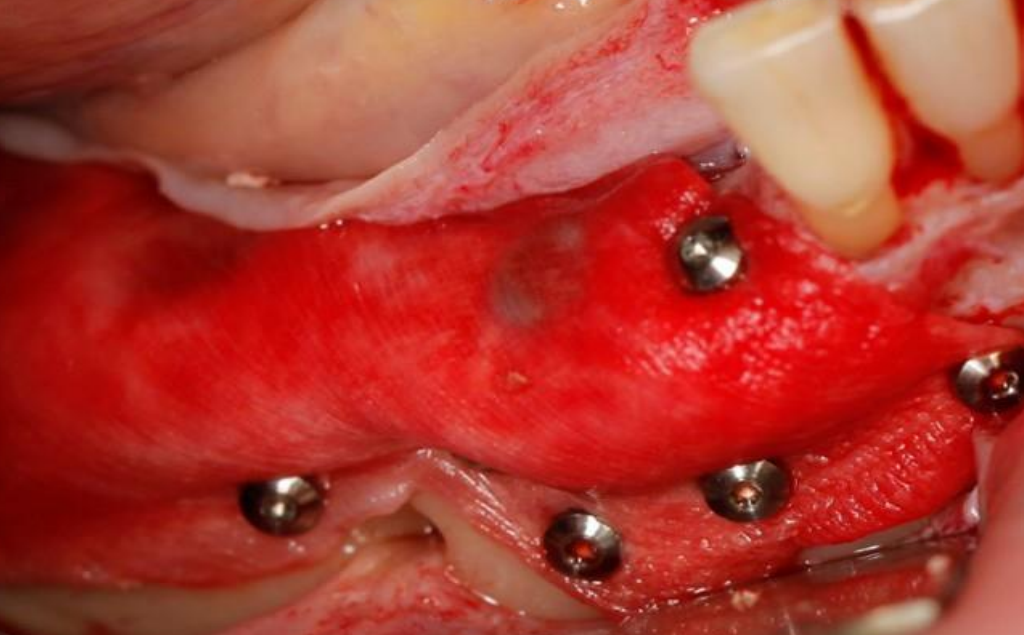

Szkolenie koncentruje się na przewidywalnych i bezpiecznych technikach augmentacji, w tym horyzontalnej i pionowej regeneracji kości, z dużym naciskiem na praktykę – uczestnicy wezmą udział w trzech warsztatach na preparatach zwierzęcych oraz zabiegach pokazowych (wideo), obserwując pracę doświadczonych wykładowców krok po kroku.

15:00 – 16:15 – Technika „Sausage Technique” jako złoty standard w horyzontalnej regeneracji kości – zasady oraz Tips&Trics.

16:30 – 18:00 – Warsztat, Technika Sausage (samodzielne wykonanie zabiegu na preparacie zwierzęcym).

9:30 – 11:30 – Zabiegi na żywo lub VIDEO z zabiegów regeneracji kości.

15:15 – 16:45 – Warsztat. Wszczepienie implantu z jednoczasową regeneracją kości (samodzielne wykonanie zabiegu na preparacie zwierzęcym).